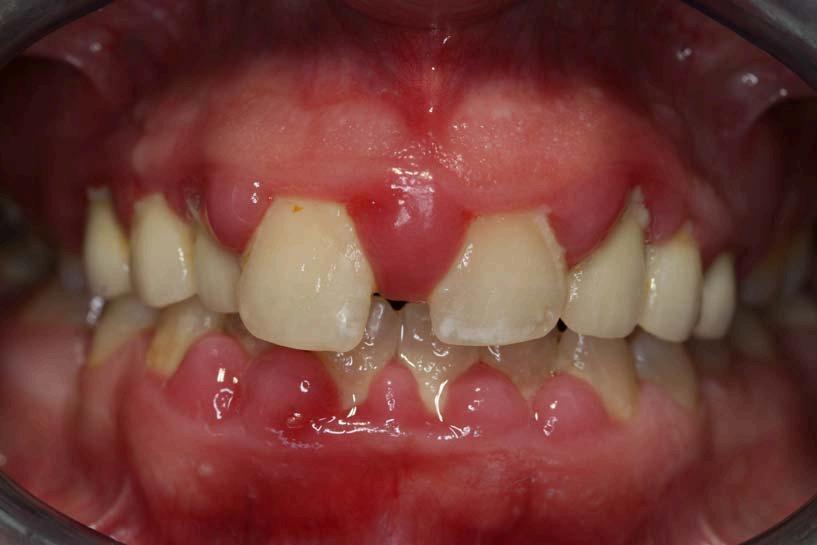

Es una infección grave de las encía que daña el tejido blando alrededor de los dientes. es una infección grave de las encías que daña el tejido blando alrededor de los dientes. Si no se trata, puede destruir el hueso en el que se apoyan los dientes, lo que puede causar que los dientes se aflojen o incluso se produzcan pérdidas dentales

Si no tiene una buena higiene la placa y el sarro se acumulan en la base del diente, esto hace que la encia se inflame y esta misma se distancie de la superficie dentaria dando paso a una bolsa periodontal. Estas se llenan de bacterias provocando infecciones, si estas continuan con el tiempo, al final destruyen los tejidos y el hueso al rededor del mismo, asi perdemos estabilidad y sustencion de nuestro diente.

Sintomas

Encias rojas o inflamadas

Dolor, sangrado en las encias

Dolor al masticas

Dientes flojos o sencibles